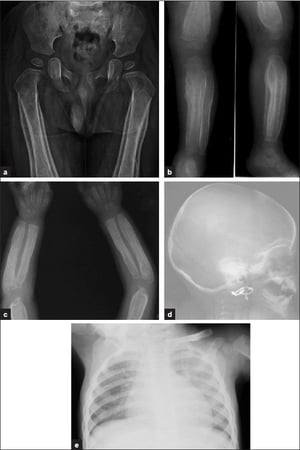

Un análisis esquelético es un conjunto de radiografías que estudia los principales huesos del cuerpo. Incluye el cráneo, los brazos, las piernas, las costillas, la columna vertebral, la pelvis, las manos y los pies. El objetivo de las radiografías es ver si su hijo tiene algún problema en los huesos. La cantidad de radiografías dependerá de la edad del niño.